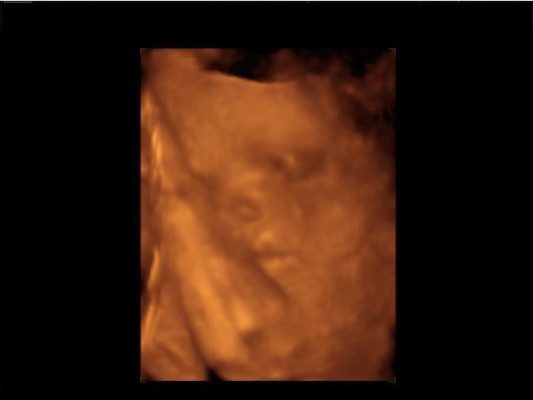

Kép

Ő Bogi, 1055 gramm és különböző méretei alapján 27 hetesnek mondták. Megint egy héttel többnek, mint az előző vizsgálatkor :) Szóval növöget szépen és Apuci nyomdokaiba szeretne lépni.

Kicsit azért meg is ijedtünk, mert némi aritmiát vélt a doki felfedezni, de amikor ő is látta, h mi most nagyon bepánikoltunk, akkor mondta, h nem kell rögtön rosszra gondolni, ez lehet teljesen átmeneti és ártalmatlan, olyasmi, mint az újszülötteknél a szívzörej és a 28. heti UH-n újra nézik, akkor valószínüleg már nem is lesz. Hát, remélem is. Szegény Apa teljesen kész volt, azt hittem nekem kell hazavinnem őt. Én úgy vagyok vele, h tudom, h nem lehet baj és nem is szeretném ezen idegesíteni magam a következő két hétben. Minden rendben van és lesz!